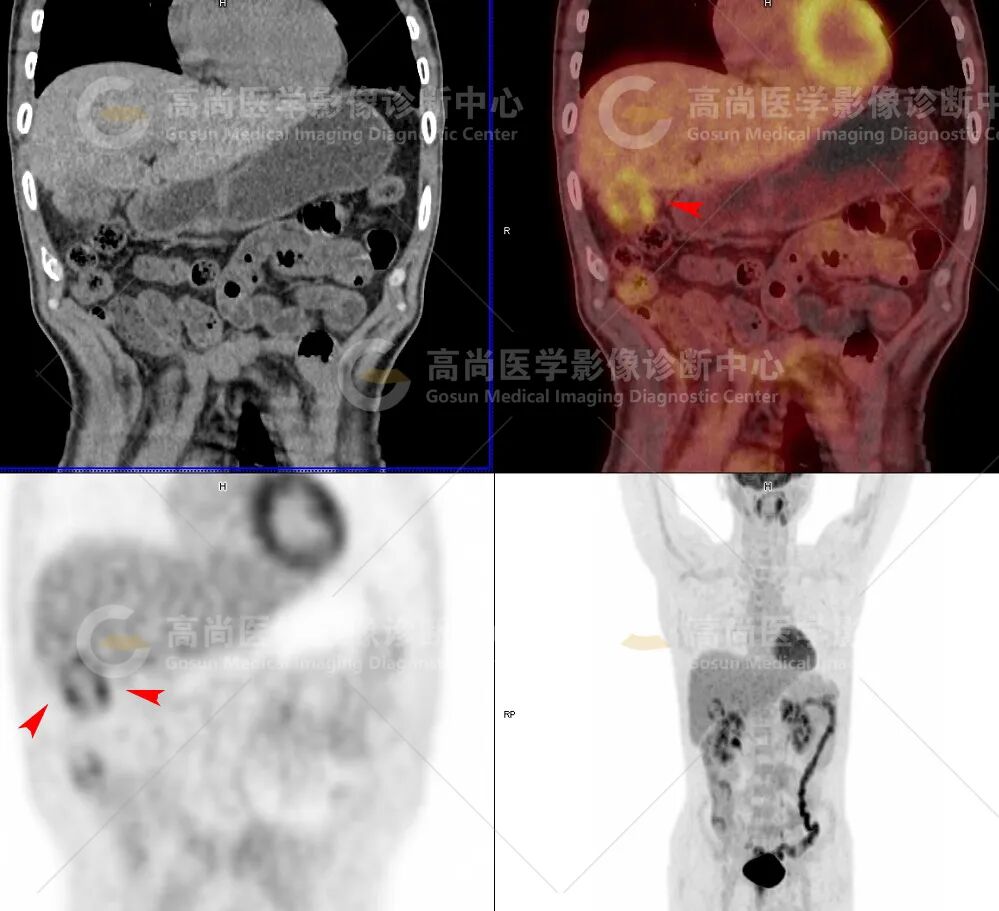

1、检查图像:

2、影像诊断: 胆结石并慢性胆囊炎 (其中胆囊底壁不均匀增厚并局部糖代谢不均匀增高,提示黄色肉芽肿性胆囊炎可能性大,不完全除外局灶性恶变可能);邻近脂肪间隙模糊,符合局部脂膜炎并腹膜炎,邻近肝脏组织粘连。